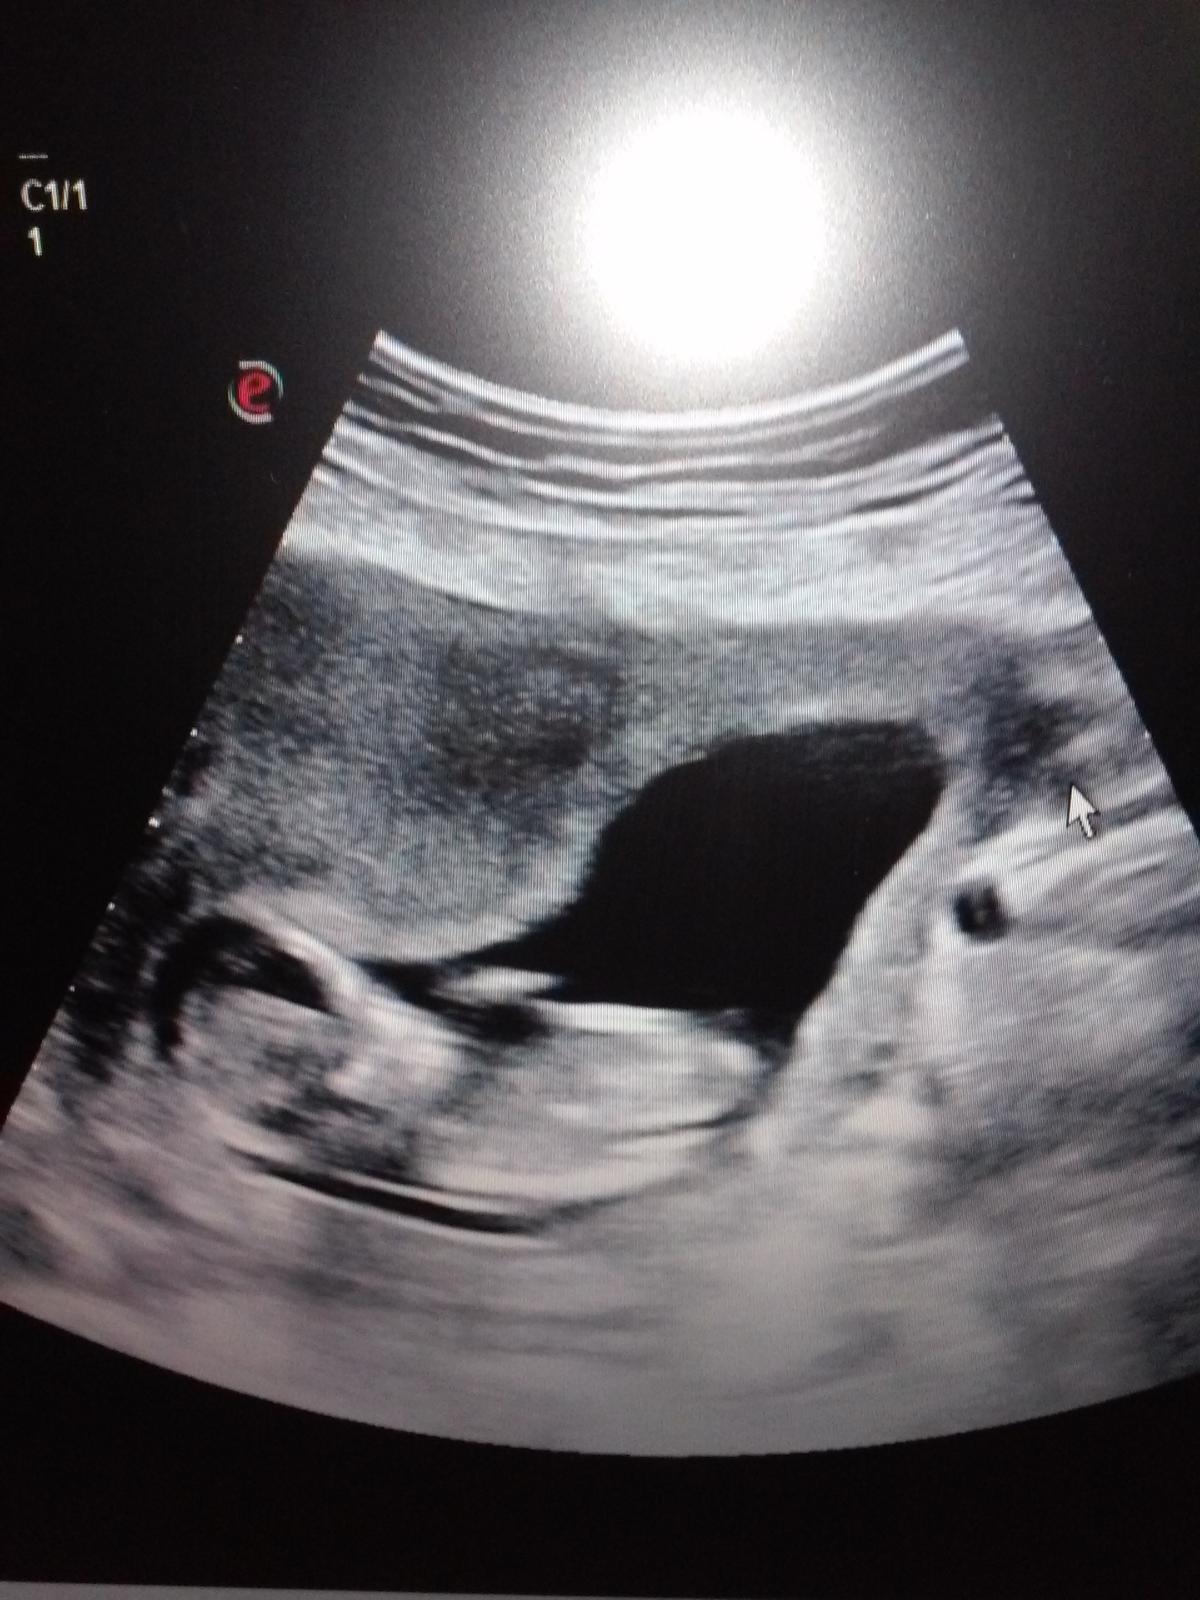

Ahojte zienky,takže dnešný ultrazvuk aj poradňa dopadli v poriadku som 12+4tt presne na chlp podľa menstruacie, ďakujem za podporu a tu je nás drobcek.... :-)